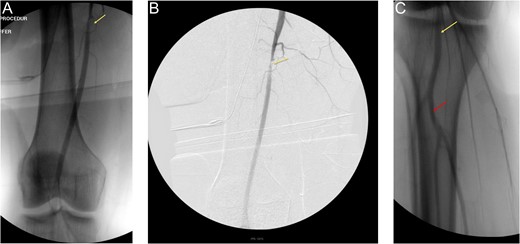

In OR, a horizontal groin incision was performed with dissection carried down to the right femoral artery and vein. After proximal control was achieved, intra-operative Doppler ultrasound of the popliteal, posterior tibial and dorsalis pedis vessels yielded triphasic signals. An on-table angiogram through the right common femoral artery depicted flow through the SFA and profunda femoral arteries with no active extravasation (Fig. 1A and B).

(A) and (B) are on-table angiograms depicting flow through SFA, without any contrast extravasation. (C)— On-table angiogram depicting flow from popliteal artery to trifurcation, without any contrast extravasation.

Although there was filling defect noted on Fig. 1B, contrast was shown flowing to the popliteal artery and thereby into the trifurcation of the right lower extremity (Fig. 1C).